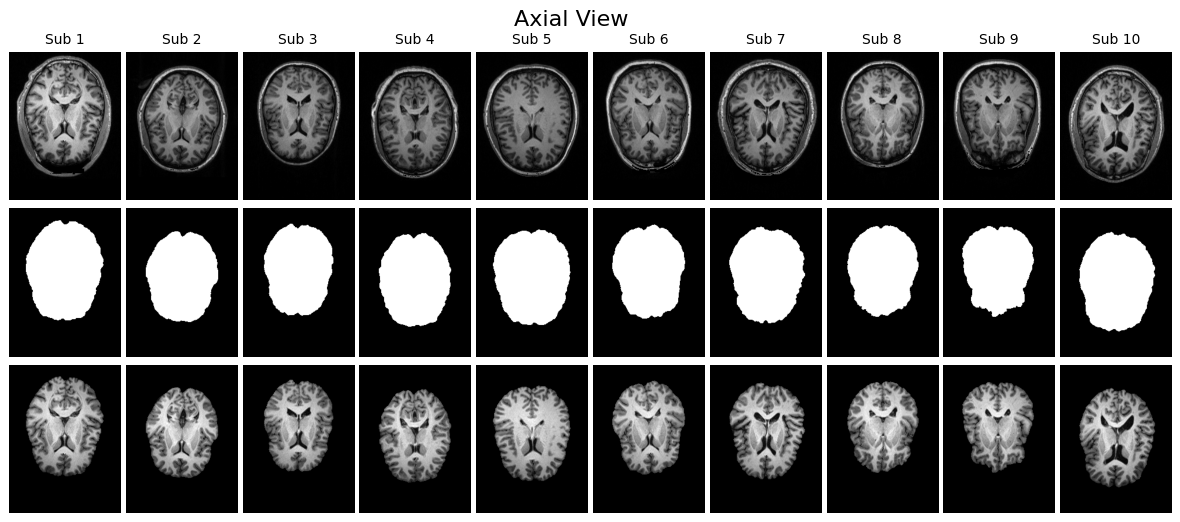

MRI データを読み込んだら、まず「本当に正しく読み込めているか」を確かめることが最初に行うべき作業です。医用画像は三次元のボリュームデータであり、単に配列の shape(形状)を確認するだけでは、脳の構造がきちんと反映されているのか、マスクが対応しているのかを判断することはできません。そのため、可視化による目視確認が欠かせません。

確認方法としては、Z 軸方向の中央スライスを取り出すのがわかりやすいアプローチです。MRI は縦・横・奥行きの三方向にスライスが存在しますが、その中央部分を選ぶことで代表的な断面を観察できます。このスライスを用い、以下の三種類を並べて可視化すると、入力とラベルの関係が直感的に理解しやすくなります。ひとつ目は元の T1 強調 MRI 画像で、脳だけでなく頭蓋骨を含んだオリジナルの状態です。ふたつ目は、その MRI にマスクを適用し脳組織のみを抽出した画像です。三つ目がマスク画像そのもので、白が脳、黒が非脳組織を示すラベル画像です。

さらに、こうした可視化を一人分だけでなく複数の患者について横並びに表示すると、データのばらつきやマスクの位置のずれがないかを効率的にチェックできます。axial(軸位)、sagittal(矢状)、coronal(冠状)の 3 断面で表示することで、読み込んだ配列に異常がないか、ファイルが壊れていないかを一目で確認できます。

こうした目視確認は「前処理や学習を進めてよいかどうか」を判断する品質チェックでもあります。この段階でマスクがオリジナル画像とうまく重なっていなければ、その後どれだけ高度なモデルを学習させても正しい結果は得られません。

visualize_slices_horizontal(voxels, labels, view='axial', n_patients=10)

visualize_slices_horizontal(voxels, labels, view='sagittal', n_patients=10)

visualize_slices_horizontal(voxels, labels, view='coronal', n_patients=10)